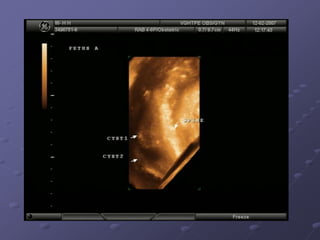

Ultrasound: An advanced ultrasound can also detect

signs of spina bifida.

Ultrasound: An advancedultrasound can also detect signs of spina bifida. Amniocentesis An analysis indicates the level of AFP present in the amniotic fluid. A small amount of AFP is normally found in amniotic fluid. when an open neural tube defect is present, the amniotic fluid contains an elevated amount of AFP because the skin surrounding the baby's spine is gone and AFP leaks into the amniotic sac. MRI